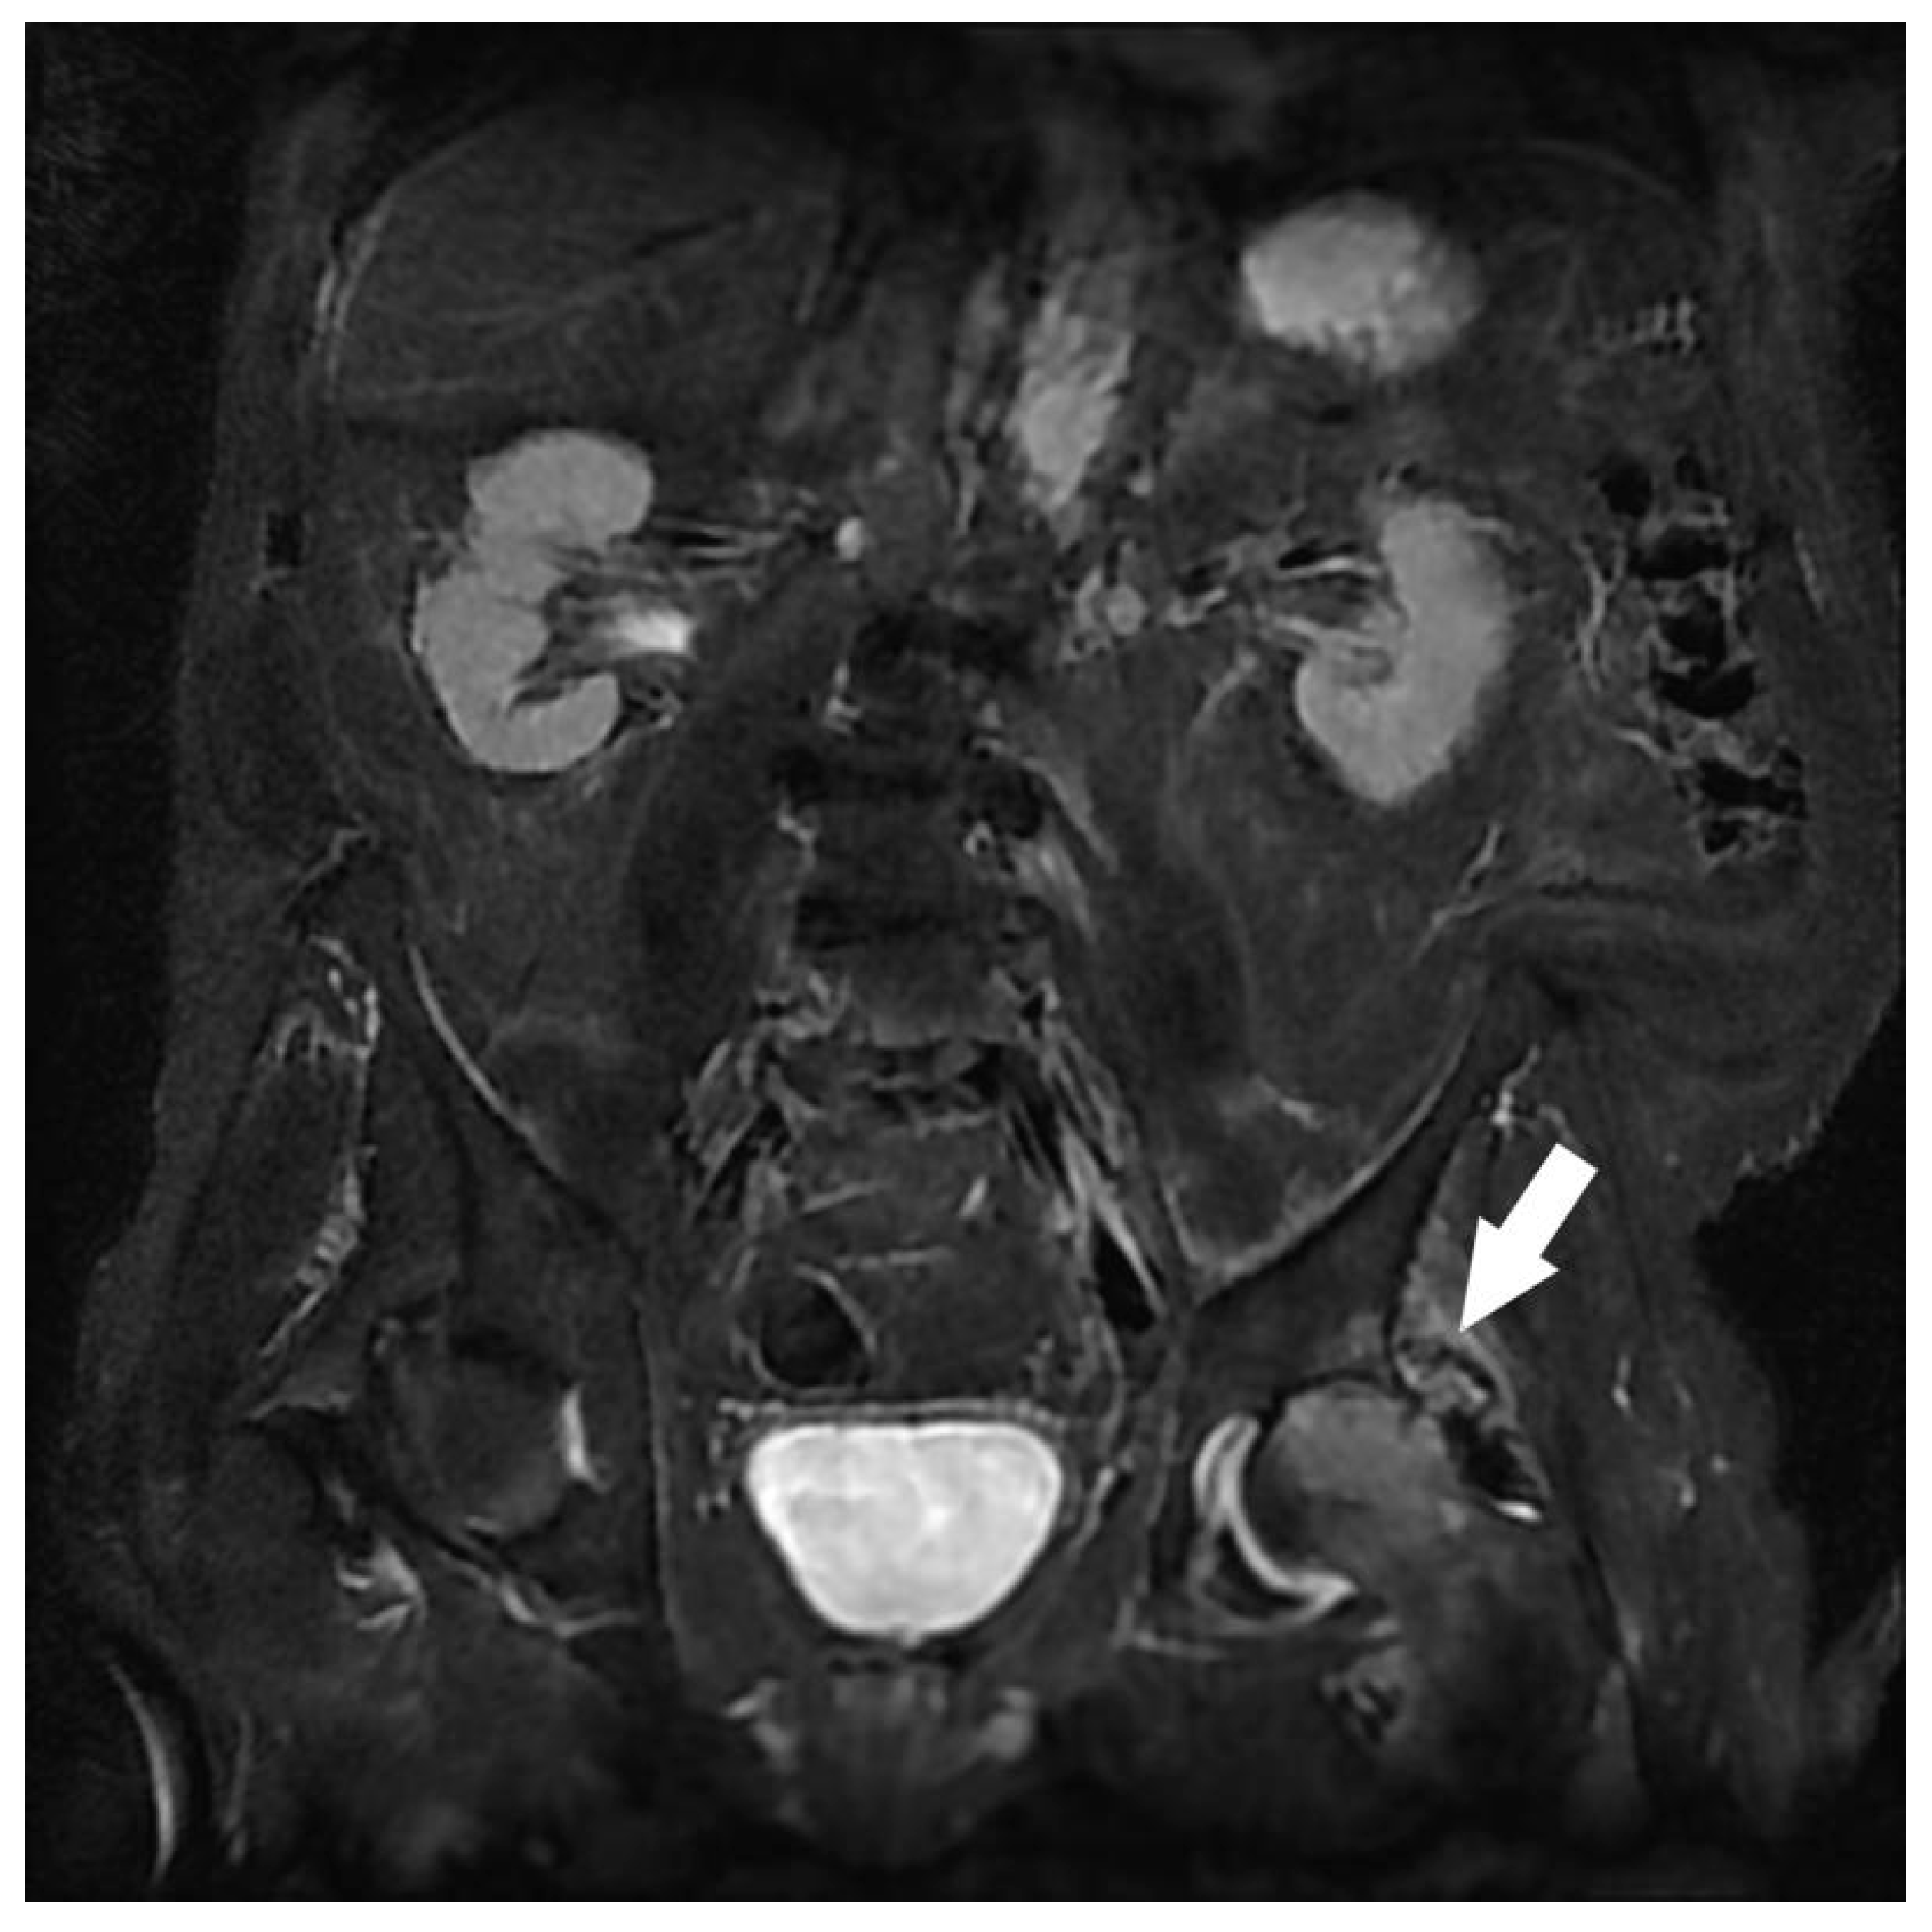

| Kidney | Atypical renal lesion 1 | 9 |

| Multicystic dysplasia, Polycystic kidney disease | 5 | |

| Pelvis | Cystic or non-cystic ovarian lesion 1 | 15 |

| Atypical uterine myoma 1 | 2 | |

| Indeterminate pelvic mass 1 | 1 | |